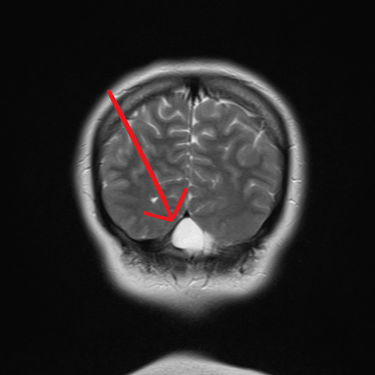

El quiste aracnoideo suboccipital es una lesión benigna de origen congénito, formada por una acumulación de líquido cefalorraquídeo entre las membranas aracnoideas. Aunque en muchos casos puede ser asintomático y detectarse de manera incidental, también puede producir cefalea, mareos, alteraciones del equilibrio o compresión del cerebelo y tronco encefálico. La resonancia magnética (RMN) es el estudio de elección, ya que permite definir la localización, tamaño y sus efectos sobre estructuras adyacentes. Este diagnóstico es clave para establecer la conducta terapéutica, que puede variar entre seguimiento clínico-radiológico o tratamiento quirúrgico en casos sintomáticos o de crecimiento progresivo.